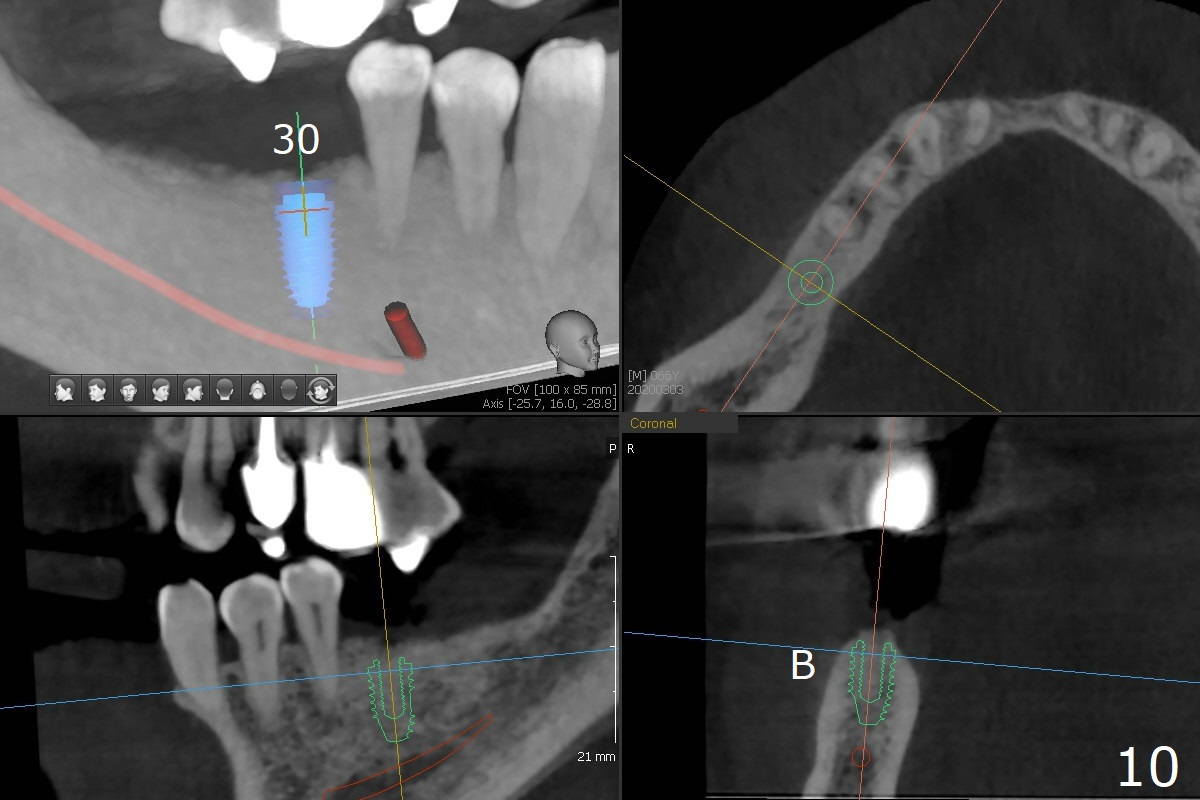

When implants at #4, 13 and 14 are placed, the patient wonders how many more implants are needed. From 0 (considering a lower RPD) to 5 (#3, 19, 20, 25 and 30). The tooth #3 seems to have periodontal-endodontic disease (Fig.1,2). Since the ridge is narrow at #19 and 20 (Fig.3), ridge split at #19 and a 1-piece implant at #20 are planned (Fig.4,5-9). The implant at #19 will be placed in an ideal prosthetic position (Fig.5). The ridge transverse bony cut will be made free hand in the middle (Fig.6,6'), followed by 2 vertical cuts and 1 apical transverse one in the 1st stage of procedure. In order to rotate the buccal block easier (Fig.6 pink curved arrow), the apical transverse cut will be wedge in shape (Fig.6 (red), 6' (double lines), 7 (black)). In the 2nd stage, the ridge top split will be extended by using a chisel (Fig.7 longer red line) and the buccal block will be pushed buccally (Fig.8). A guide will be seated to finish osteotomy (Fig.9 white) and implant placement.

While the ridge at #30 is normal for a normal sized implant (Fig.10,11), the one at #25 is not (Fig.12, a 2 mm 1-piece implant).